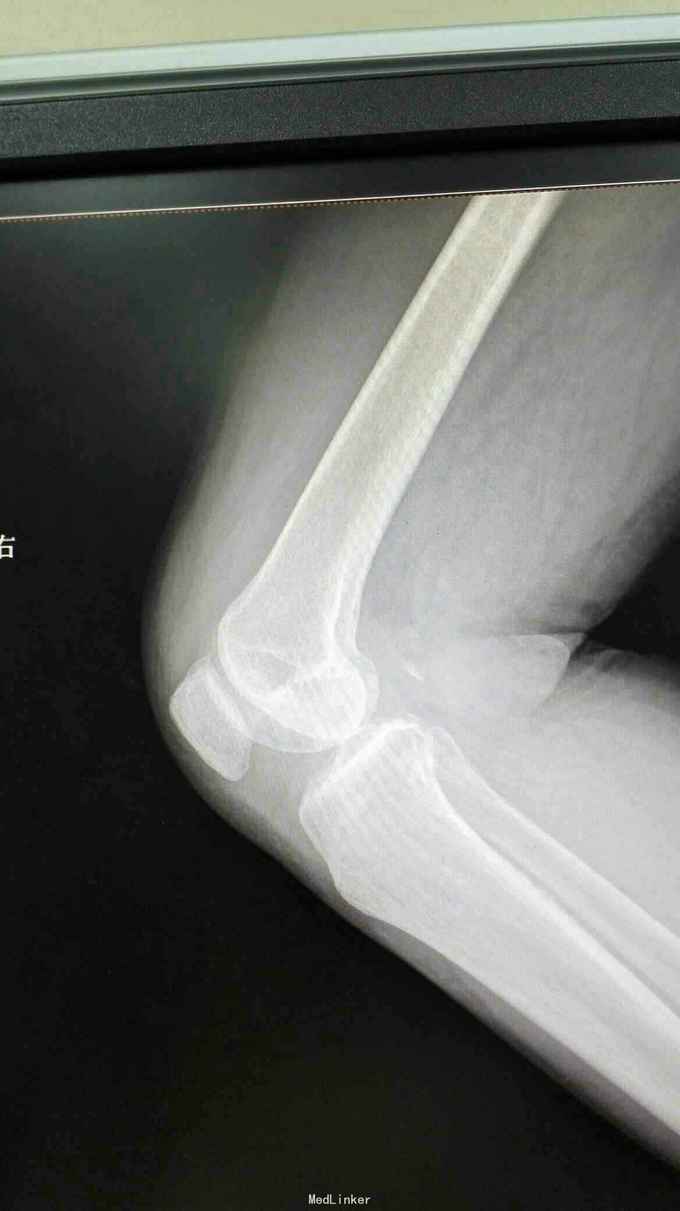

右膝外形正常,皮温正常,右膝内前方压痛(+),前后抽屉试验(-),侧方应力试验(-)、研磨试验内侧(+),关节活动度正常,左膝正常。 站立位膝关节正侧位片提示:右膝关节轻度退行性变,内侧关节间隙稍变窄 右膝关节MRI提示:右股骨内侧髁水肿,考虑局部骨坏死 实验室检查:各炎症指标均正常

诊断:1、右股骨内侧髁骨坏死 2、右膝关节骨性关节炎 治疗:行右膝关节单髁置换术